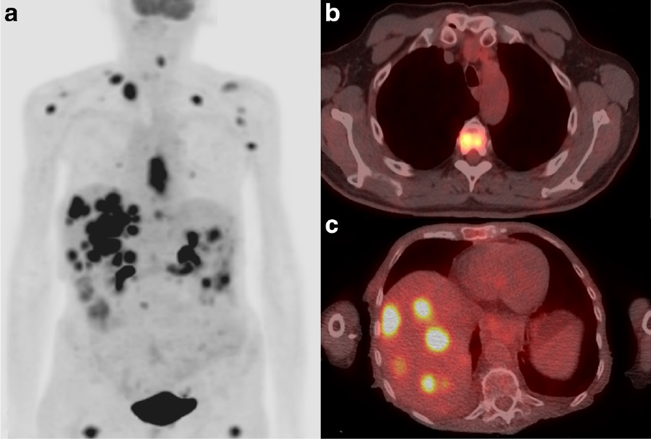

漫威系列电影大家应该都至少看过几部,里面超级英雄的命名基本都很能反映人物自身能力特点:一身铁壳子叫钢铁侠,浑身冒绿光叫绿灯侠,目光咄咄逼人就叫镭射眼。但有一个人的名字似乎并不直白——死侍,这位老哥并非刀枪不入,也没啥高科技,其实是靠着一身生物医学的本事——“可控式肿瘤细胞分裂”,在超级英雄队伍中占了一席之地。死侍堪称打不死的小强,三五个持枪硬汉突突不死,身体被钢力士撕成两半也能重新长出一个下半身,因为没了对象多次抑郁到自寻短路,最后都以满血复活告终。说句不好听的,按照超能力来命名,死侍其实应该叫“肿瘤侠”。关于他的超能力是咋回事,这一切还要从女娲无限造人(误)可以无限分裂的肿瘤细胞讲起。二十世纪早期,诺贝尔奖获得者Alexis Carrel一直是细胞研究领域的权威,他声称自己做了一个长达34年的实验,证明从鸡身上提取出来的细胞,在体外可以连续培养的时间,比鸡本身活的还长。换而言之,细胞分裂是永恒的、不受限的。这个细胞无限分裂的理论一度风靡全球,使得当时主流生物学界认为,在适宜条件下,细胞是“永生”的。可是,如果构成生物体的细胞可以永生,每个人不都成了活神仙?生物本身怎么还会有寿命限制?其实,我们体内的大多数细胞,无论是来自皮肤、血液或肝脏,确实会不断分裂,更新换代。不过,负责更新换代的“干细胞”通常只能分裂几十次,之后就会逐渐衰老、凋亡,当人体内大部分具有分裂能力的细胞都发生这种变化时,就表现为器官功能的下降,以及整个人体的衰老。那么,真的有能够无限分裂的细胞吗?还真有,肿瘤细胞就是这样的终极存在。在衰老过程中,如果基因突变的积累导致细胞遗传物质的改变,一些“老不死”的细胞——肿瘤细胞,就会产生,它们不再遵循正常细胞分裂分化的规律,自己想怎么整就怎么整,要是在早期没被发现,就会形成癌症,危及生命。事实上,“不老不死”只是肿瘤细胞最容易观察到的特点之一。不同来源的肿瘤细胞,还拥有很多其他共性,比如“不听指挥”——不受人体正常生长信号的调控;“乔装打扮”——逃脱人体内免疫细胞的追杀;“东逃西窜”——在人体侵袭和转移的能力;“食欲旺盛”——大量消耗葡萄糖,等等。正常细胞在分裂时一分为二,而肿瘤细胞由于基因调控异常,常常表现为一个分裂成多个,比如图中所示的“三足鼎立”,每个子细胞都会疯狂抢夺母细胞的物质。|来源:作者自己养的细胞不知道大家有没有听说过曾经风靡一时的“饿死癌细胞”的说法?非蠢即坏的营销号和低智媒体声称,可以通过控制饮食饿死肿瘤细胞而不损伤正常细胞,从而治愈癌症。这实际上正是基于肿瘤细胞“食欲旺盛”的特点造出来的谣。相比于正常细胞,肿瘤细胞由于能量代谢通路改变,对葡萄糖的需求量会大大提升。但仅凭这一特点,完全无法单纯通过控制饮食对肿瘤细胞造成任何影响,在它们被饿死之前,更加脆弱的正常细胞,怕不是已经被饿死十遍了。尽管如此,肿瘤细胞“吃得多”的特性确有用武之处。临床上常用的PET-CT检查,正是利用了肿瘤细胞的这种特点,把带有放射性同位素标记的葡萄糖注射到人体内,显示出代谢速率明显提升的肿瘤所在位置。PET-CT可以显示疑似肿瘤的高代谢病灶。|来源:PhysicsWorld多年以来,人们很自然地认为,宏观上整个肿瘤的糖消耗提升,是因为内部每一个肿瘤细胞消耗了更多的糖。虽然肿瘤内除了肿瘤细胞还有很多种免疫细胞,比如髓细胞和淋巴细胞,但它们的“胃口”似乎不如肿瘤细胞大。一些研究表明,也许正是肿瘤细胞大量消耗了周围环境中的葡萄糖,导致肿瘤内部的免疫细胞营养供给不足,代谢受到影响,没办法发挥正常的免疫清除功能,杀死肿瘤细胞。俗话说,“兵马未动,粮草先行”,粮食不够,肯定打不赢。然而,4月7日,在《自然》杂志发表的一项最新研究中,科学家使用包括结直肠癌、肾癌、乳腺癌在内的六种不同肿瘤模型,反复进行体内与体外实验,结果发现了一个颠覆传统认知的有趣现象:在这些肿瘤中,消耗糖最多的并不是肿瘤细胞,而是免疫细胞。他们把小鼠身上长出来的肿瘤分成一个个细胞,再把所有细胞分门别类,分别测定每种细胞的平均耗糖量,发现肿瘤内部的免疫细胞其实比肿瘤细胞还“贪婪”,吃糖吃的最多,而肿瘤细胞更喜欢一种叫“谷氨酰胺”的物质(一种氨基酸,蛋白质的基本组成单位之一),吃了之后,还能反过来抑制糖的代谢通路。这一发现,让人不禁直呼“好家伙”,原来肿瘤细胞也不傻,知道糖吃多了不行,要多摄入蛋白质!(一个不严谨的玩笑)肿瘤细胞更喜欢吃一种叫“谷氨酰胺”(Glutamine)的氨基酸。|来源:mskcc.org不过,这样的营养分配机制到底对肿瘤的生长有啥用?是不是所有肿瘤都有这样的共性?这对肿瘤的治疗有啥指示意义?目前我们还不是很清楚。在类似的问题得到科学证据回答之前,只希望不会有一篇名为《震惊!科学家发现肿瘤细胞新特性,乏氨基酸饮食或可治愈肿瘤》的文章出现在大众视野里。如果列举本世纪人类最大的愿望清单,“治愈肿瘤”一定是其中之一。想治愈肿瘤,势必要足够了解肿瘤。之前说了,人类的生长和衰老过程中,细胞多次分裂导致的基因突变累积,是肿瘤产生的根本原因,这也是为什么人一到五六十岁,各种肿瘤的发生率会直线上升。当人类了解了天花的致病机理,就发明出方法消除了天花,那现在人类也了解了肿瘤的产生原因,有没有希望完全消除肿瘤呢?在《癌症:进化的遗产》一书中,作者写到,基因突变是生物进化的原动力,同时也是肿瘤细胞产生的根本原因。只要有细胞分裂,就会发生基因突变,就会有肿瘤细胞生成。换句话说,肿瘤细胞是进化过程中不可避免的副产物,从这个角度来讲,根除肿瘤细胞似乎是不可能的。然而,不能根除肿瘤细胞,并不意味着不能治愈肿瘤,只要人类能找到方法,在肿瘤细胞大肆增殖繁衍、形成肉眼可见的肿瘤之前发现它们,并予以恰当的治疗,肿瘤也许就能像感冒一样,吃点药就能控制了。脑洞更大一点,如果人类真的在足够了解了肿瘤细胞之后,能设法操纵其分裂,那电影中死侍跟金刚狼“瞬间愈合”的超能力,也许将不再是无稽之谈。